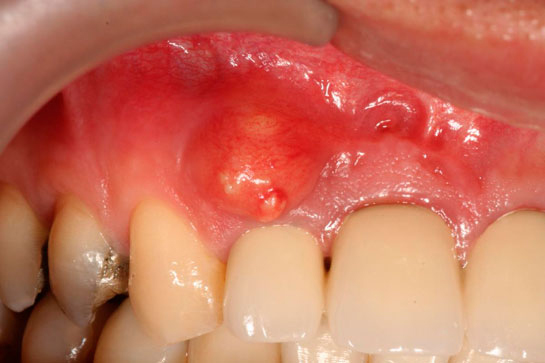

Olası Komplikasyonlar Diş çekimi sonrasında bazı komplikasyonlar gelişebilir. Bu komplikasyonlar arasında şunlar yer almaktadır: